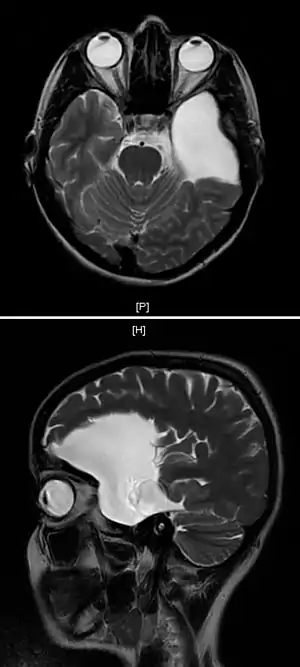

Diagnosis

Diagnosis is principally by MRI. Frequently, arachnoid cysts are incidental findings on MRI scans performed for other clinical reasons. In practice, diagnosis of symptomatic arachnoid cysts requires symptoms to be present, and many with the disorder never develop symptoms.